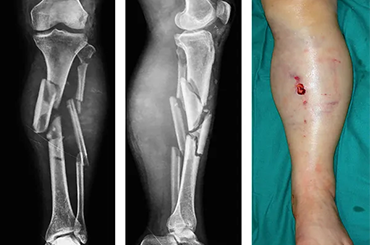

Complex Fracture

Complex fractures are characterized by the severity of bone fragmentation and the involvement of adjacent tissues such as muscles, blood vessels, and nerves.A complex fracture refers to a severe break in a bone that presents multiple challenges compared to simpler fractures. These fractures often involve multiple fragments, damage to surrounding tissues, or complications that complicate the healing process.